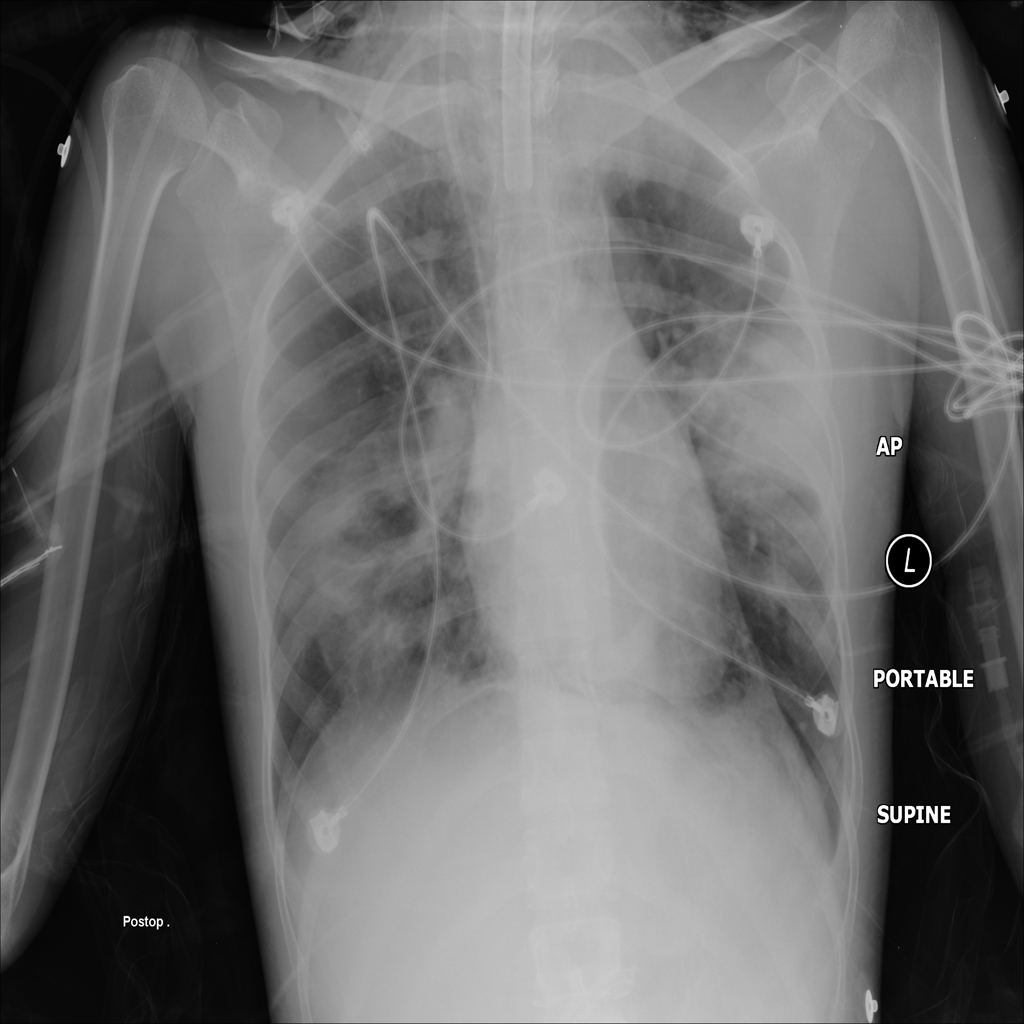

PAT-55FC · IMG-031Emphysema

PAT-55FC · IMG-031

AP